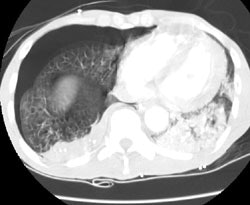

Computed Tomography: On CT the pleural thickening or calcification is clearly identified. Thickened lung markings and vessels swirl into the lesion which abuts the pleural surface ("comet tail sign"- central bronchovascular pedicle)- however, this finding may be absent in up to 8% of cases. Curvilinear air bronchograms are often visible within round atelectasis. The lesion is very commonly based or tethered by a strand to a thickened pleural surface. Pericicatril emphysema may also be seen. Volume loss within the affected lung is also common- often characterized by displacement of the fissure bounding the affected lobe. Calcification may also be found within areas of round atelectasis (up to 25% of cases)- possibly secondary to engulfment of a granuloma within the atelectatic lung, or invagination of a calcified pleural plaque. The lesion will enhance homogeneously after the administration of I.V. contrast (up to nearly 90% of cases). Inhomogeneous enhancement is atypical for rounded atelectasis [12].

Round atelectasis on PET FDG imaging: The images below demonstrate the typical CT and FDG PET findings in round atelectasis. On CT, there are thickened lung markings and vessels which swirl into the lesion that abuts an area of pleural thickening. Note the lack of metabolic activity in round atelectasis on PET imaging. |